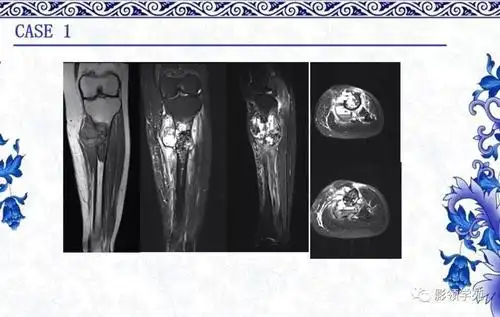

【经典】常见骨源性肿瘤的影像表现_骨膜